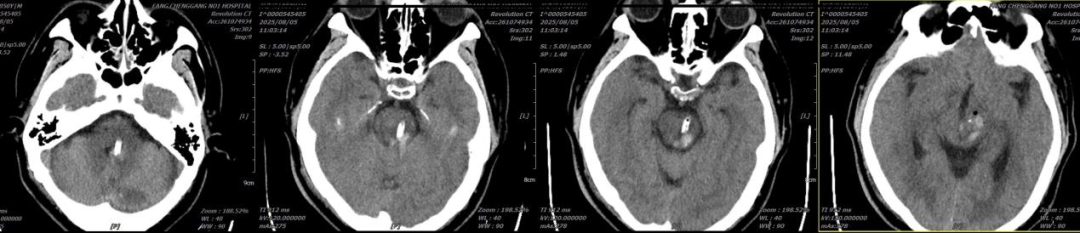

▲术后CT检查